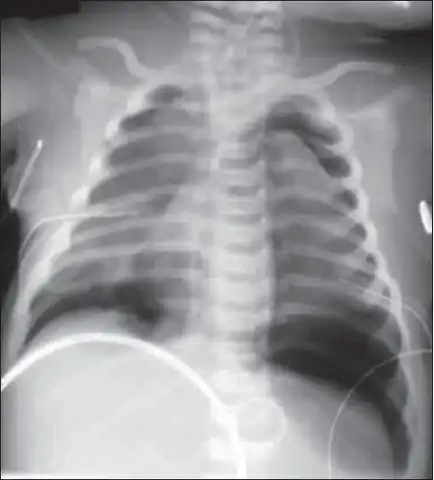

| X-ray showing lung damage in response to meconium in a newborn. | |